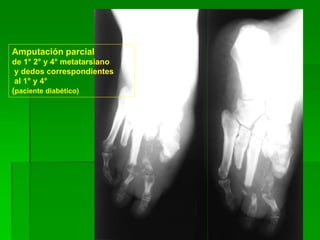

Amputación:

Parcial de primer dedo

y total del cuarto

Calcificación

de pared vascular

Amputación parcial

de 1° 2° y 4° metatarsiano

y dedos correspondientes

al 1° y 4°

(paciente diabético)